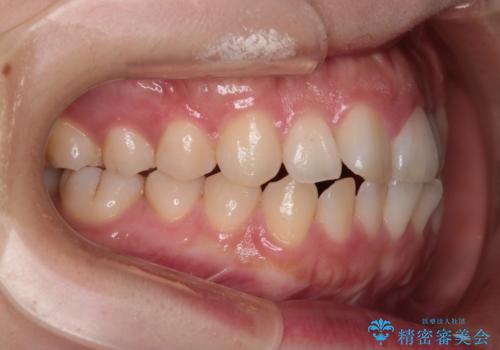

【インビザライン】前歯の凸凹を治したい

- 前歯の凸凹を主訴に来院されました。

インビザラインにて臼歯部の遠心移動を行いながら、できるだけ前歯が出ないように気を付けて治療を行っています。

遠心移動を行う必要があったので、患者様には顎間ゴムを使用していただきました。